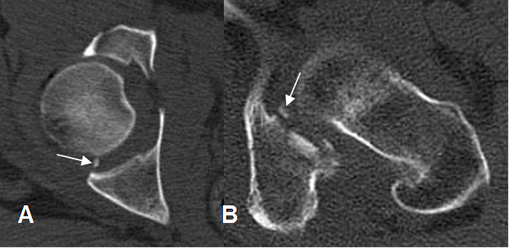

Fig 58. Fractura de acetábulo. Igual paciente anterior.

TAC axial. Fractura del reborde acetabular anterior izquierdo, no sospechada con la Rx simple.

En el lado derecho se aprecian las fracturas ya descritas.